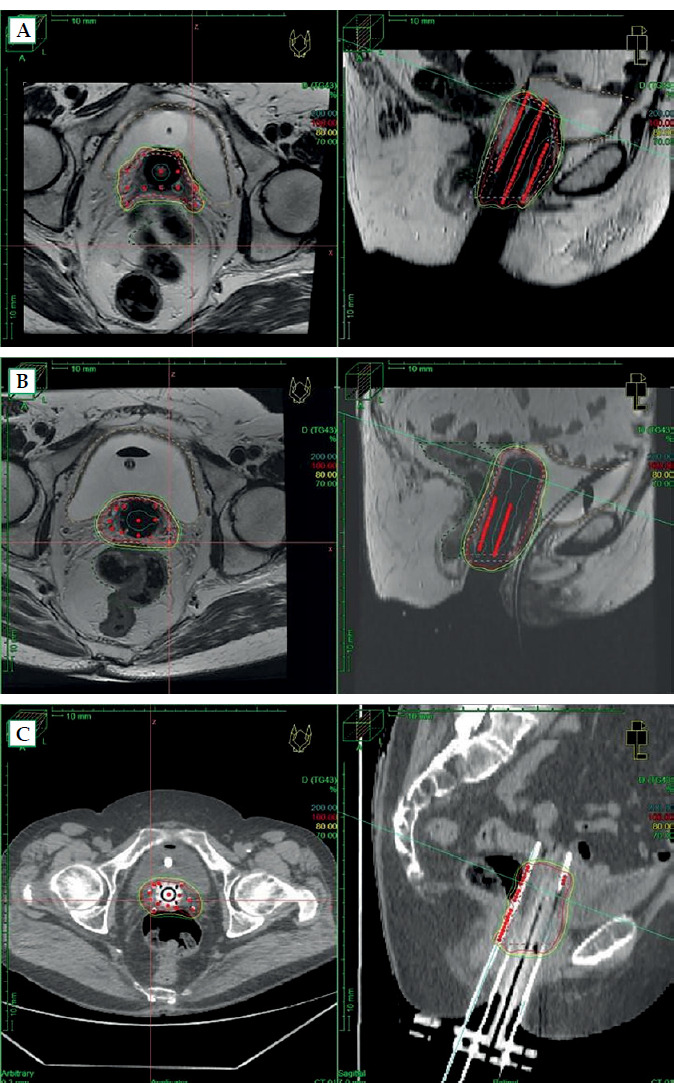

Purpose: The purpose of the study was to analyze patients with vaginal-involving recurrences of gynecological tumors and primary vaginal tumors, treated with transperineal interstitial brachytherapy (P-ISBT). Dosimetric, clinical, and toxicity analysis of these patients was conducted, incorporating MRI in volume definition and dose-volume dosimetry.

Material and methods: Forty-two patients were retrospectively analyzed. They were treated with radical or adjuvant intent (in hysterectomized patients with high-risk of relapse). P-ISBT was performed with MUPIT (CT-based planning) in 18 patients (42.9%) and with Template Benidorm (TB) (MRI-based planning) in 24 patients (57.1%).

Conclusions: MRI-based planning is superior to CT-based planning in P-ISBT. It allows for better definition of CTV, resulting in smaller and more selective treatment volumes. Our results show a tendency towards higher D90 CTV dose and lower rectal/bladder D2cc dose, leading to less events of late rectal toxicity.